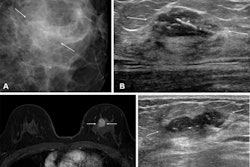

The use of preoperative breast MRI to improve surgical staging has increased, especially among women with dense breasts, extensive ductal carcinoma in situ (DCIS), and lobular histology, the team explained. But Black women are less likely to undergo this exam -- putting them at risk of additional surgery. Ginzberg's group investigated whether the use of preoperative MRI after breast cancer diagnosis varies by race and insurance type and whether undergoing the exam is associated with downstream surgical management.

The authors referred to a number of studies that have shown disparities in the use of MRI after breast cancer diagnosis, citing four that found that the likelihood of undergoing preoperative MRI before breast cancer treatment was higher for white women compared to Black women. They noted that these studies did not adjust for breast density, "a key characteristic that influences the clinical value of breast MRI and is also correlated with patient race."